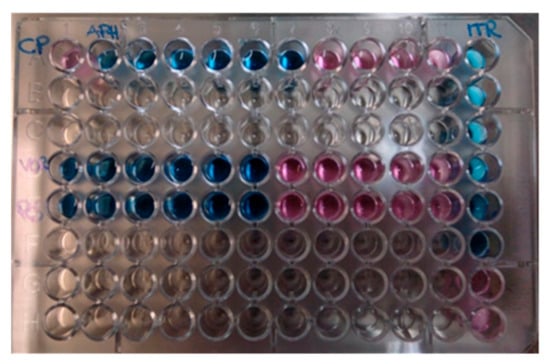

Two days later, the serological diagnosis was confirmed by broth microdilution plates of blood cultures coming back positive for C. neoformans with a high sensitivity to Amphotericin B (minimum inhibitory concentration, MIC: 0.5 μg/mL), Posaconazole (MIC: 0.25 µg/mL), Voriconazole (MIC: 0.25 µg/mL), and Itraconazole (MIC: 0.125 µg/mL) (Figure 2). The detection of C. neoformans was performed using the Maldi toff (Becton Dickinson, Four Oaks, NC 27524, USA) system, the automatic system for microbial identification using mass spectrometry (Figure 2), while the VitekS2 and out the Micronaut-AM system (Merlin broth test in microdilution system) was used for the sensitivity test (Figure 3 and Table 2).

Figure 3.

Broth microdilution plates of blood cultures. In blue: sensible concentration. In red: resistant concentration.